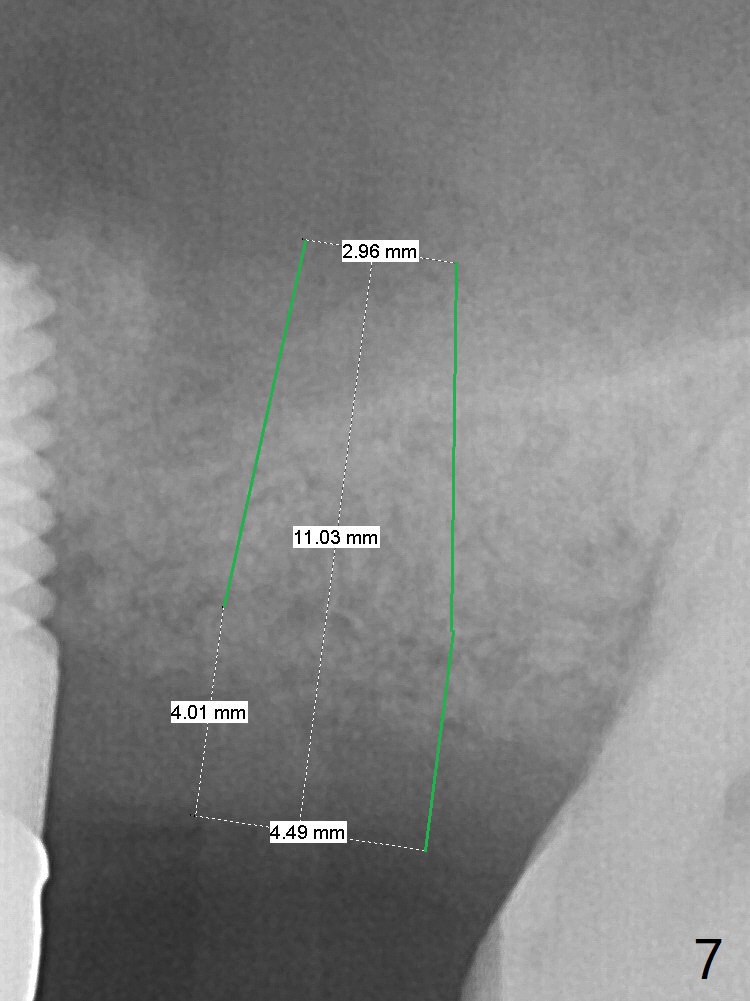

A 32-year-old woman develops periimplantitis (severe hemorrhage and deep pockets) at #14 three years 7 months post cementation (Fig.1).  A 4.5x11 mm implant is placed with flap at #13 after failure for the 1st time (Fig.2), while a 5x11 mm implant is placed flapless with sinus membrane perforation.  Uniposts are cemented with Ketac.  The lingual plate at #14 is defective (Fig.3).  The implant at #14 will be removed flapless, followed by Osteogen plug (most likely sinus floor defect) and bone graft.  After healing, an implant will be placed with guide.  By breaking the proximal contacts, the crown, abutment and implant at #14 are shaken loose using forceps.  Finally the crown breaks off.  Make a slot on the top of the abutment and use a screw bit to turn the abutment/implant counterclockwise.  There is abundant granulation tissue with arterial hemorrhage associated with granulation tissue removal.  The defect involves the distal surface of the implant at #13 and the mesial surface of the tooth #15.  Therefore bone graft is deposited in these surfaces (Fig.4 arrowheads, as compared to preop BW, Fig.4').  The periodontal dressing seems to remain in place asymptomatic 7 days postop (Fig.5).  The bone height 5.5 months postop should be enough for implantation (Fig.6).  To avoid marker associated with guided surgery, free hand will be adopted.  Sinus lift with PRF is expected.  To place in the middle of the ridge buccopalatally, incision will be made with bone expansion.